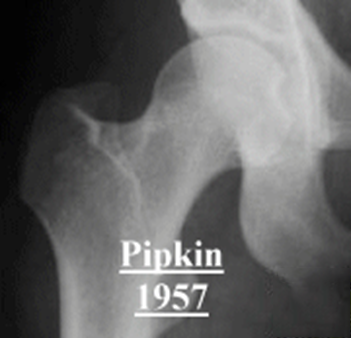

(3)Pipkin 骨折

髋关节后脱位往往合并股骨头骨折(5-15%)。最早(1957 年)由 Pipkin 描述并分类,因而被命名为 Pipkin 骨折,常见于屈膝屈髋位汽车仪表盘损伤。